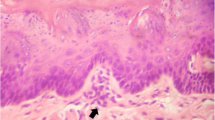

Photomicroscopy of the oesophagus. A Normal oesophageal epithelium (male animal of the inhalation control group). B Mild oesophageal dysplasia. There is a slight increase in the thickness of the epithelium, bulky nuclei with evident nucleoli and atypical mitosis figures (arrow) (male animal of the high inhalation concentration group). C Moderate oesophageal dysplasia. Note a marked increase in epithelial thickness, bulky nuclei with evident nucleoli and atypical mitosis figures (arrow) (male animal of the high oral concentration group). Haematoxylin-eosin, 200× magnification — scale bar: 100 μm